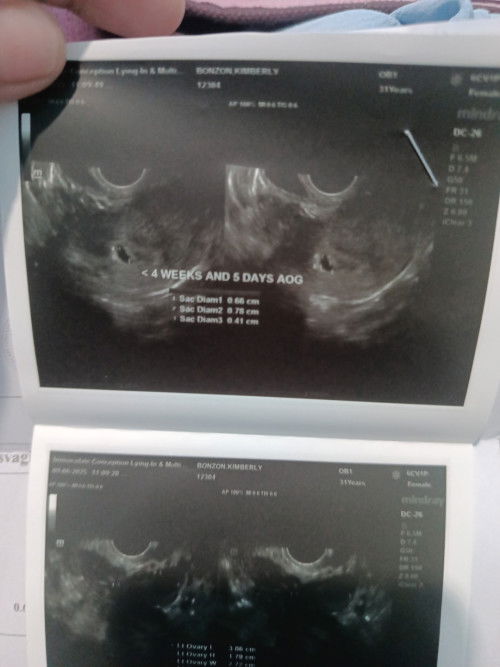

Hi mga mommies! May tanong po ako: Positive ako sa pregnancy test, pero walang nakita sa transvaginal ultrasound. Makapal na lining ng matres ko, pero bakit ganun? Buntis po ba ako? Salamat sa tulong!

hi mommy! same here. almost 1month na ako Hindi niregla. (16days delayed from my last period) nag positive din ako sa PT. pero walang nakita sa transvaginal.. and it happens na nag spotting ako. and tuloy tuloy na nagkaron ng blood Meron mga black na parang spots madami (it hurts parang dysmenorrhea pa sya). possible po ba na miscarriage Ako? thanks for the response.

buntis kana nyan nd lang nakita kasi baka ilang weeks ka palang. possible yan nd makita kapag sobrang aga ung check up ilang weeks ka palang ba

its positive. hindi lang nakita sa TVS, could be due to too early pregnancy, especially na hindi pa ganun ka-clear line sa PT mo. repeat TVS after 2-3weeks.

baka too early pa, pa tvs ka ulit after 2-3wks. For the meantime, inom ka na ng folic acid and mag ingat. wag magpaka stress,

Baka po nasa early weeks k palang po kaya d pa sya detected, balik ka po siguro around 3-4 weeks para sure

Try mo mga ilang weeks. Pag early kasi minsan di pa nbubuo yung sac nya